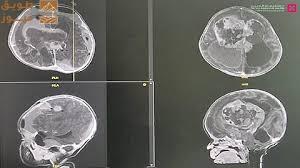

- مؤتمر الأشعة الخامس والعشرين الذي يركز على “تمكين الطب الشعاعي 2.0: الارتقاء برعاية المرضى” عبر الابتكار والتقنيات التعاونية، ويقود هذا المؤتمر الدكتور هداية علي أنصاري استشاري طب الأشعة ورئيس الطب النووي في مستشفى كليفلاند كلينك أبوظبي.